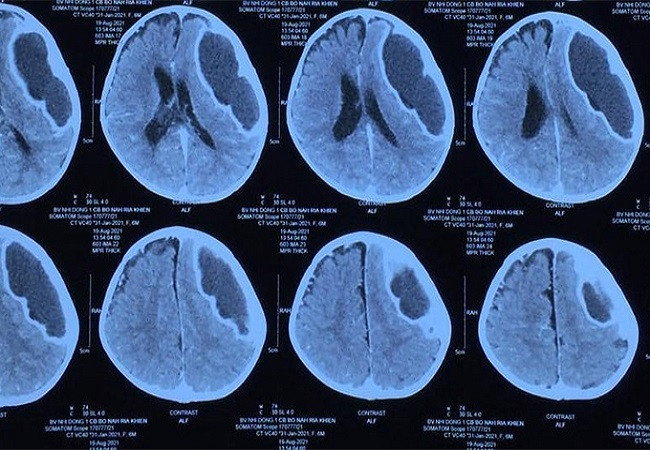

Hình ảnh khối áp xe chiếm phần lớn trong đầu bệnh nhi trước phẫu thuật. Ảnh: Vietnamnet.vn.

Qua thăm khám, chụp chiếu, các bác sĩ chẩn đoán, bệnh nhị bị áp xe não nặng. Bệnh nhi được hồi sức tích cực, phẫu thuật lấy ổ áp xe não rất lớn, chèn ép trong đầu, nguy cơ đe dọa tính mạng. Ca mổ thành công, giữ được tính mạng cháu bé nhưng cần phải theo dõi di chứng về sau.

Bao áp xe của bé đã dày như vỏ quả cam sành, có lẽ do tự dùng kháng sinh không hợp lý tại nhà. Nếu bé được điều trị đúng ngay từ đầu, diễn tiến có thể đáp ứng thuốc mà không cần phẫu thuật”, bác sĩ Trí cho biết.